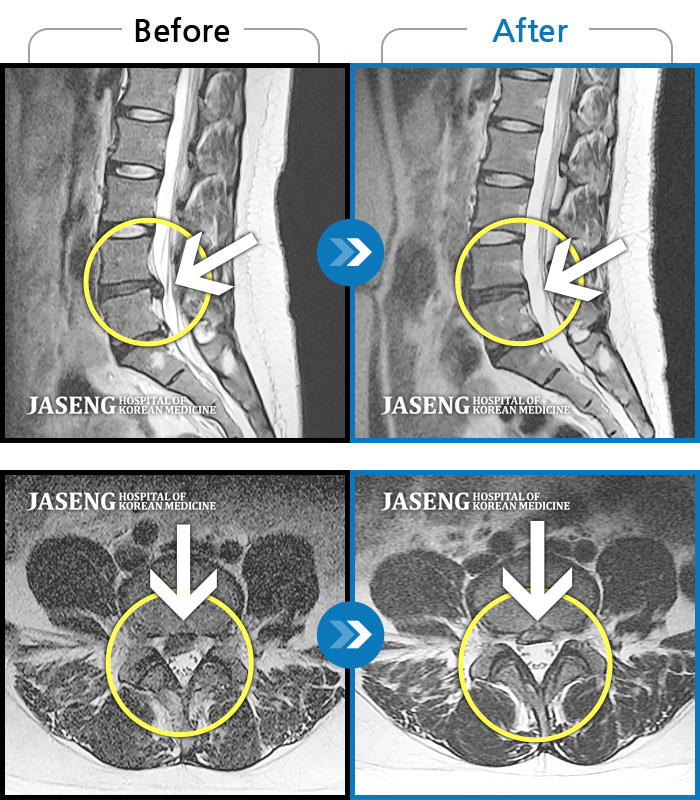

허리디스크

보라매 · 빈상은 원장

허리통증, 좌측 다리 바깥쪽으로 저림이 있어서 양말을 신기도 어려워요.

촬영시기

2022.12.12 ~ 2023.06.10

2023.11.24

조회수 181